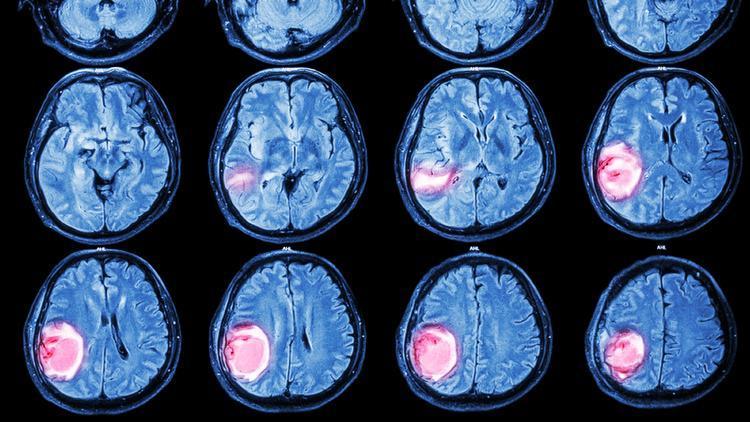

Max Wrathall spor salonunun otoparkında arkadaşlarıyla sohbet ederken, hak ettiği bir kahveyi içmek için sabırsızlanıyordu. Max, arkadaşlarıyla verdiği kısa molanın tadını çıkarıyordu, ta ki her şey kararana kadar. Yere yığılan Max aniden bir nöbet geçirdi. Bu, hayatında geçirdiği ilk nöbetti ve beyin tümörünün alınması için beş saat süren bir ameliyatla sonuçlanan korkunç bir olaylar zincirini başlatacaktı.

“Bir şeylerin doğru olmadığını biliyordum. Doktor beni Paul ile bir odaya çağırdı. Gözlerimi ve reflekslerimi kontrol etti, nasıl hissettiğimi sordu, ben de iyi hissettiğimi söyledim. Sonra dedi ki, ‘Korkarım beyninizde büyük bir kitle var.’ Bunun bir tümör olduğunu düşündüklerini söyledi. Her şeyden çok kopmuştum. İlaçlar yüzünden çok yorgun olduğumu ve neler olup bittiğinin pek farkında olmadığımı hatırlıyorum. Ama kendimi iyi ve sakin ve hissediyordum.”

Sonunda ameliyat günü geldi çattı. Beş saat süren ameliyat sırasında bir cerrah Max'in sol kulağından sağ kulağına doğru bir kesi yaptı, ardından kafatasını deldi ve tümöre ulaşmak için alnından kredi kartı büyüklüğünde bir kemik parçası aldı.

Nisan 2023'te yapılan taramanın ardından cerrahlar tümörün tamamının çıkarıldığını doğruladılar. Tümörü iyi huylu ve en az şiddetli olan 1. derece olarak sınıflandırdılar. Max, bunun 'çok büyük bir rahatlama' olduğunu söyledi.